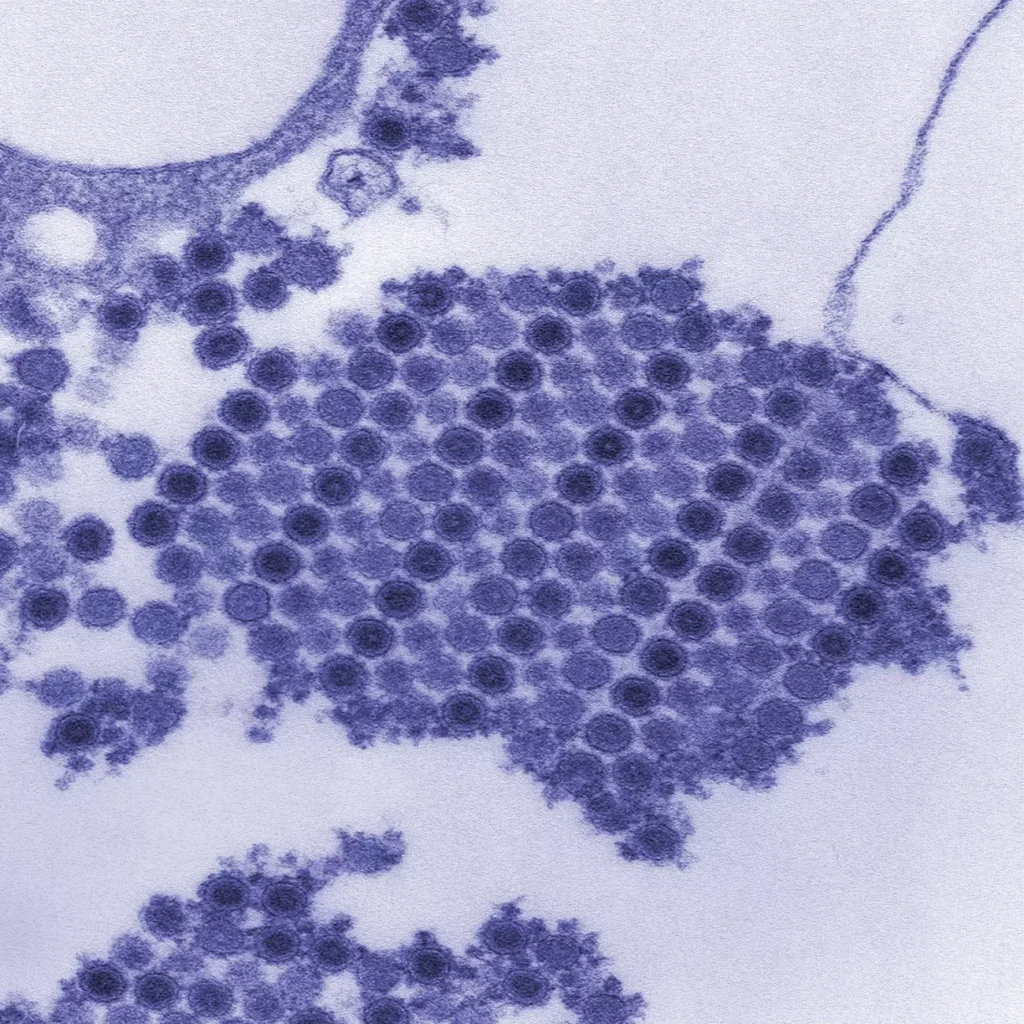

基孔肯雅熱是一種由基孔肯雅病毒引起的疾病,主要透過蚊子叮咬傳播。這種病毒主要由埃及斑蚊(Aedes aegypti)和白線斑蚊(Aedes albopictus)傳播,牠們在熱帶和亞熱帶地區活動頻繁。當帶病毒的蚊子叮咬人類時,病毒就會進入體內,導致感染。

這波爆發與季節性氣候有密切關係。春夏交替時期氣溫回升,濕度增加,為帶有病毒的埃及斑蚊(Aedes aegypti)及白紋伊蚊(Aedes albopictus)繁殖提供理想環境。積水處增多亦促進蚊群數量上升,病毒傳播風險隨之提升。此外,人流集中和戶外活動增多,加快了病毒在人群間傳播。

基孔肯雅熱主要透過帶有病毒的蚊子叮咬傳播,最常見的兩種蚊子是埃及斑蚊(Aedes aegypti)和白線斑蚊(Aedes albopictus)。這兩種蚊子白天活躍,特別喜歡在人類周圍繁殖和叮咬。